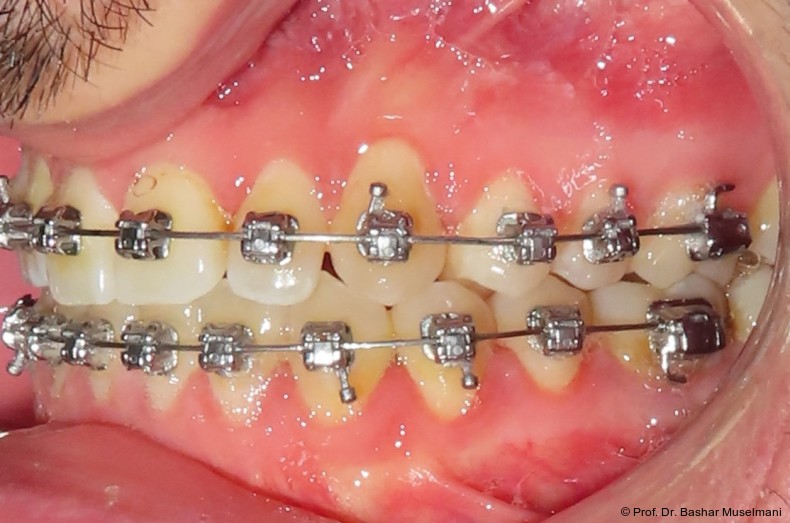

Apparative Versorgung

Die Behandlung erfolgte mittels einer festsitzenden Multibracketapparatur unter Verwendung passiver selbstligierender Brackets (Damon Ultima System) im Ober- und Unterkiefer.

Zur sagittalen Korrektur wurden intermaxilläre Klasse III-Gummizüge eingesetzt.

Bracketpositionierung und Torque-Strategie

Oberkiefer

• Zähne 12–22: Brackets mit Retroklinations-­Torque

• Zähne 13 und 23: Brackets mit proklinationsförderndem (Brocline-)Torque

Ziel war die kontrollierte Retrusion der oberen Front bei gleichzeitiger Sicherung der Eckzahnbreite.

Unterkiefer

• Zähne 33–43: Brackets mit proklinationsförderndem Torque

Hierdurch sollte eine gezielte Proklination der unteren Front zur Verbesserung des Overjets und der sagittalen Verzahnung erreicht werden.

Zu Beginn der Nivellierungsphase wurden in beiden Kiefern 0.013" CuNiTi-Bögen eingesetzt (Abb. 4a–e).